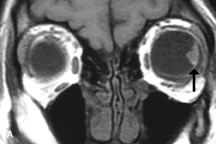

PATIENT PREPARATION Before MRI is performed, patients must be screened and prepared to avoid the potential hazards associated with the strong magnetic field. Patients who have ferrous aneurysm clips or cardiac pacemakers, who depend on life-support equipment, or who retain a possible metallic intraocular foreign body are not candidates for this imaging modality. MRI cannot be performed on obese patients who cannot fit into the bore of the magnet. Patients who are claustrophobic may not tolerate a prolonged period of study within the confines of the magnet, whereas others might do well if given a mild sedative. All worn metallic objects (e.g., necklaces, watches) should be taken off, credit cards set aside, and eye makeup removed before entering the room containing the magnet.5,20,34,35,36 NORMAL ORBITAL ANATOMY T1-weighted images provide the best anatomic details of the orbit because they display superior contrast resolution between normal structures (see Fig. 8). The vitreous has a long T1, resulting in an intermediate signal similar to brain, whereas the crystalline lens and sclera appear dark because of a longer T1 and short T2. The extraocular muscles, like all skeletal muscles, demonstrate a moderately long T1 and short T2 and highly contrast with the intense signal of the surrounding orbital fat (adipose tissue has an extremely short T1). The lacrimal glands appear as mottled areas of reduced intensity of the signal from the orbital fat in the lacrimal fossa. The optic nerves are seen with the same signal intensity as brain white matter and are hypointense relative to the orbital fat because their Tl is longer than the Tl of fat but shorter than the Tl of water. Cortical bone is not well delineated because it contains little free water, yielding minimal signal in MRI, and thus appears dark on all pulse sequences. This feature explains why MR images of the orbital apex and intracanalicular portion of the optic nerves are superior to comparable CT scans. Partial volume averaging of the bones in these regions obscures soft tissue details on CT images, whereas MRI reveals the signals only from the soft tissue structures with no cortical bone input. Bone marrow, on the other hand, is seen as a relatively intense signal because of its high fat content (see Fig. 8).37,38 T2-weighted pulse sequences are not ideal for imaging normal anatomy; however, they are particularly useful in revealing pathologic conditions (see Fig. 9). T2-weighted studies are most easily recognized by a bright vitreous signal. ORBITAL DISEASES Vascular Lesions Cavernous hemangiomas appear as well-circumscribed, smooth, usually intraconal masses that are isointense to muscle on T1-weighted images and hyperintense on T2-weighted images (Fig. 12). Patchy early enhancement is typically followed by diffuse, more homogeneous enhancement.39 The internal architecture of the mass, including septation and internal vasculature, may often be appreciated with high-quality orbital imaging.40 Lymphangiomas consist of ectatic vascular channels within a connective tissue stoma with varying degrees of lymphoid cellularity. On MRI, these tumors are typically poorly circumscribed, multicompartmental, and heterogeneous, often showing cystic dilations with fluid levels (Fig. 13). The signal characteristics within lymphangiomas vary considerably, reflecting cystic and solid components and the varying paramagnetic characteristics of blood at different stages of degradation.40–42 Acute hemorrhage appears hypointense on both T1- and T2-weighted formats. Methemoglobin present in subacute hemorrhage (3 to 14 days) leads to hyperintense signal on both T1- and T2-weighted images.41 A small percentage of lymphangiomas appear radiologically indistinct from orbital cavernous hemangiomas.43 Orbital varices are venous malformations that expand with increased systemic venous pressure, such as with Valsalva maneuvers. Because rapid acquisition of images during a Valsalva maneuver is important in imaging such a lesion, conventional or spiral CT is currently the modality of choice.44 MRI is an excellent modality for demonstrating enlargement of the cavernous sinus and dilation of the superior ophthalmic vein in patients with high-flow carotid-cavernous fistulas (Fig. 14).37MRA may be helpful in the evaluation of the venous outflow pattern. The rapidly flowing blood in these vascular structures carries the excited protons out of the section before they can be imaged, resulting in their dark appearance.5 In low-flow dural arteriovenous malformations, MRA may help define the arterial feeding vessels.45 Neural Lesions MRI is more effective than CT in delineating the intracranial optic nerves, chiasm, and optic tracts and, for this reason, is the preferred imaging modality in the evaluation of optic nerve disorders. The spatial relationships and image contrast of the orbital tissues with intraorbital optic nerve tumors is comparable between the two imaging modalities. The normal nerve is isointense to brain and appears enlarged and kinked owing to infiltration of an optic nerve glioma on T1-weighted images. Gliomas appear hyperintense on T2-weighted images and may be heterogeneous owing to cystic areas within the tumor. Contrast enhancement is variable.46 Intraorbital and intracranial optic nerve sheath meningiomas are usually isointense to cortical gray matter on Tl-weighted images and remain isointense on proton density studies (Fig. 15). Gd-DTPA is useful in delineating the intracranial extension of optic nerve meningiomas.7,47 The hyperostosis of bone and calcification associated with meningiomas are not demonstrated as well on MRI studies as on CT scans.20,37 Gd-DTPA–enhanced MRI also appears promising in the study of the permeability of the blood–brain barrier in selected optic neuropathies.22,48 MRI may reveal an enlarged optic nerve and some degree of contrast enhancement in cases of optic neuritis.49 Muscle Disorders Extraocular muscle enlargement in patients with thyroid-associated orbitopathy is demonstrated equally well with CT and MRI studies. However, the superior tissue contrast on MR images reveals better details of the relationships of the optic nerve to the thickened muscles at the orbital apex (Fig. 16).50 In addition, MRI may be able to differentiate between muscles that are enlarged as a result of edema and active inflammation and those enlarged because of fibrosis by their T2 relaxation times.21 Quantitative MRI was not found to be accurate in predicting the success of low-dose orbital irradiation.51 However, a muscular index relating the diameters of the rectus muscles to the bony orbital dimensions was useful in predicting optic nerve compression.52 MRI is also effective in imaging orbital tumors of mesenchymal origin, such as rhabdomyosarcoma, particularly in the assessment of extension into the anterior and middle cranial fossae (Fig. 17).37 The lack of any pathognomonic radiologic features necessitates rapid orbital biopsy when rhabdomyosarcoma is suspected. Osseous Lesions In general, CT is the imaging modality of choice when details of quantity and quality of bone are needed; however, abnormalities of bones can be detected indirectly by MRI. Cortical bone appears black (signal void) on MR images because of its low proton density and free-water content. The absence or discontinuity of the signal void of the orbital walls may represent bony destruction or fracture. Hyperostosis associated with prostate metastases or meningioma is visualized as areas of black smudging.50,53 Diseases in which the bone is replaced by pathologic tissues with a high free-water content, such as fibrous dysplasia, are well demonstrated on MRI. An intermediate signal intensity on T1-weighted images and hypointense signal on T2-weighted images is representative of fibrous dysplasia. Enhancement on post–Gd-DTPA MR scans is seen and is more evident in areas that are less mineralized.54 Cystic Lesions Dermoid cysts appear as rounded, well-defined lesions typically contiguous with an orbital bony suture. The high-intensity signal on T1-weighted images is attributed to the sebaceous-produced lipid contents (Fig. 18).31,50 Mucoceles may demonstrate a hypointense or hyperintense signal on MR images, depending on the concentration of proteinaceous or inflammatory fluid components. The integrity of the bony walls of the expanded sinus cavities cannot be assessed on MR as well as by CT.37,50,55,56 A high-signal intensity on Tl- and T2-weighted images is characteristic of orbital chronic hematic cysts because of the blood-breakdown products within the cysts.57 Trauma Although soft tissue relationships are usually better demonstrated on MRI, the evaluation of craniofacial bony trauma is preferable with CT. For example, prolapse of orbital fat through a fracture site and hemorrhage of adjacent tissues are demonstrated in an MR image, but the actual fractured bone is not imaged. Three-dimensional MRI of the orbit in subacute trauma has been described,58 although its precise role is not currently established. MRI has been suggested to be superior to CT in detecting intraorbital wooden foreign bodies.59,60 In a series of penetrating orbital injuries with organic foreign bodies, however, MRI was able to identify the foreign body in only four of seven cases.61 With an in vitro model for wood foreign body, McGuckin and colleagues concluded that CT was the imaging modality of choice.62 A careful history and, in selected cases, plain films to rule out a metallic foreign body are crucial before MRI is considered in patients with periocular trauma. MRI is particularly helpful in the detection and characterization of subperiosteal hematomas of the orbit (Fig. 19). They are most commonly seen in the subperiosteal space of the superior orbit as well-defined masses following a traumatic injury. The signal intensity varies depending on the acute, subacute, or chronic nature of the hematoma, based on the stage of blood degradation. Fresh hemorrhages are hypointense on T1-weighted images and hyperintense on T2 images. Hematomas that are 1 to 7 days old are hypointense on both T1- and T2-weighted images. T1-weighted images of hematomas more than a week old are hyperintense due to the oxidation of deoxyhemoglobin to methemoglobin, whereas the T2 images remain hypointense.63 Metastatic Tumors Breast carcinoma metastatic to the orbit has been demonstrated to be hypointense to the surrounding orbital fat on T1-weighted studies and hyperintense on T2-weighted images and has an affinity to the extraocular muscles (Fig. 20).50,64 The MRI characteristics of prostate carcinoma metastatic to the orbit have been described as involving the greater and lesser wing of the sphenoid, orbital roof, and optic canal. Diffuse bone hypertrophy with isointense or slightly hyperintense tissue on T1-weighted images represents the osteoblastic carcinomatous bone infiltration. Contrast enhancement is variable on T1-weighted and fat-suppressed images.65 Most other metastatic tumors also have a lower intensity signal on T1-weighted images and appear to displace or infiltrate normal orbital structures; however, their signal characteristics are variable on T2-weighted MR images.66 Many metastatic tumors demonstrate bright contrast enhancement with Gd-DTPA. Infectious Disorders MRI findings of preseptal and orbital cellulitis typically include increased signal intensities on T2-weighted images of the eyelids and orbital fat, respectively, due to the increased water content of the tissues. Since most cases of bacterial orbital cellulitis are associated with paranasal sinusitis, hyperintense signals of the affected sinuses may also be found on T2-weighted images as well as enhancement of polyps and granulation tissue on postgadolinium T1-weighted MR images. Subperiosteal abscess formation may occur due to contiguous spread of infection from the paranasal sinuses and appear on MRI as an area of intermediate signal on T1-weighted and proton-weighted MR images. The abscess may appear slightly hyperintense compared with muscle on T2-weighted scans with the necrotic contents having the greatest intensity.67 MRI and MRV are more sensitive than CT in revealing cavernous sinus thrombosis. Engorgement of the cavernous sinus, extraocular muscles, and ophthalmic veins is seen with hyperintensity of the thrombosed sinuses evident on all pulse sequences. The enlarged, thrombosed superior ophthalmic vein appears less hypointense than the normal contralateral ophthalmic vein, and hyperintensity within the lumen of the vessel may be seen on T1- and T2-weighted MR images.68 Inflammatory and Lymphoproliferative Lesions Inflammatory conditions of the orbit, both idiopathic (inflammatory pseudotumor) and those of known causes, have been found to be hypointense to fat and isointense to muscle on Tl-weighted studies and isointense or slightly hyperintense to fat on T2-weighted images (Fig. 21).50,64,69 The more fibrous or sclerosing varieties have less signal intensity on T2-weighted images. Marked enhancement is seen in pseudotumor infiltrates after gadolinium administration.70 The same signal characteristics are demonstrated in patients with Tolosa-Hunt syndrome, with mass lesions seen in the cavernous sinuses and orbital apices.71 Lymphomas have MRI characteristics similar to those of inflammatory lesions in that they are hypointense to fat and isointense to muscle on T1-weighted images (Fig. 22). They may appear hyperintense to fat on T2-weighted images, perhaps owing to less fibrosis than that seen in orbital inflammatory pseudotumor, although this is not a consistent finding.31,50,66 Lymphoid tumors typically enhance moderately after contrast injection. Unfortunately, studies have shown that tumor density and homogeneity are similar between inflammatory and malignant orbital infiltrates, and MRI cannot differentiate these lesions.72,73 Lacrimal Gland Tumors Lacrimal gland lesions present special problems in diagnosis and management. Pleomorphic adenoma (benign mixed tumor) should not be biopsied, but rather excised in toto. On the other hand, for lymphoma and inflammatory infiltrates, incisional biopsy is more appropriate than complete excision of the lacrimal gland. Thus, preoperative clinical and radiologic evaluation are especially crucial in planning appropriate surgical management. Pleomorphic adenomas demonstrate long T1 and T2 signal characteristics. They may show heterogeneity on T2-weighted images74 and moderate to marked enhancement with contrast.75 Signal characteristics of adenoid cystic carcinoma include hypointensity to fat on T1-weighted images, hyperintensity to fat with increased T2 weighting, and isointensity to fat on proton density-weighted studies (Fig. 23).31,75 Secondary bony alterations of the lacrimal fossa associated with lacrimal gland tumors, such as remodeling (benign mixed tumor) or destruction (adenoid cystic carcinoma), are seen indirectly on MR images; however, bone windows on CT scans provide better delineation of these changes. In contrast to the round or globular appearance of benign or malignant epithelial tumors of the lacrimal gland, lymphoproliferative tumors usually appear to be molding or draping onto the globe and the surrounding bony orbit. LACRIMAL DRAINAGE SYSTEM DISORDERS MRI with surface coils provides excellent spatial resolution and tissue-specific signal intensities of the lacrimal drainage system. These parameters have been found useful to more accurately demonstrate the extent of lesions in the lacrimal sac and differentiate long-standing mucoceles from solid tumors than CT.76 Physiologic studies in patients with tearing disorders now include MR dacryocystography, in which Gd-DTPA is either placed topically in the conjunctival fornix or injected by cannulation into the lacrimal sac. They provide a detailed morphologic and functional analysis of the lacrimal excretory system; however, they are no more sensitive than digital-subtraction dacryocystography or CT dacryocystography.77–79 INTRAOCULAR TUMORS On MRI, uveal melanomas have a typical appearance that helps to differentiate them from other primary and secondary intraocular tumors as well as choroidal detachments. Pigmented melanomas are hyperintense on Tl-weighted images, hypointense on T2-weighted studies, and hyperintense on proton density–weighted examinations (Fig. 24).30,31,50,80–82 These signal characteristics have been attributed to the paramagnetic properties of melanin because of stable free radicals that shorten the T1 and T2 relaxation times. Moderate enhancement is seen on postgadolinium T2-weighted images. Gadolinium-enhanced T1-weighted images are particularly sensitive in detecting choroidal melanomas.83 MRI may be less sensitive in detecting extrascleral extension of tumor than echography performed by an experienced ultrasonographer.84 Tumors metastatic to the choroid are hyperintense on T1- and T2-weighted images.24 The signal characteristics, however, may be similar to those seen with choroidal melanoma. Choroidal hemangiomas, on the other hand, have an intermediate signal on T1-weighted sequences and become hyperintense on T2-weighted images50 as well as proton density–weighted images.81 Retinoblastomas display moderate signal intensity on T1-weighted studies and a low signal on T2-weighted images.31,80,85 Calcification can be easily detected by CT and ocular ultrasonography but is not imaged by MRI.25,50 The presence of optic nerve involvement is best evaluated by MRI. ACQUIRED ANOPHTHALMIA When an eye is removed owing to tumor or trauma, an implant is typically placed in the intraconal space. MRI may be useful in defining the size, shape, and position of such orbital implants.86 Porous hydroxyapatite or polyethylene implants are preferred by many surgeons performing enucleation or evisceration. A porous implant offers the possibility of supporting a motility coupling peg to increase the movement of the overlying prosthesis. MRI with contrast is used by some surgeons to evaluate the degree of fibrovascular ingrowth in hydroxyapatite87 and porous polyethylene88 implants prior to motility peg placement. |